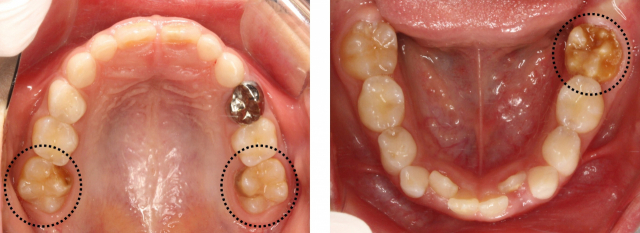

앞니와 어금니 쪽이 황색이나 갈색으로 변색되거나 치아 일부가 떨어져 나가는 증상이 치아 저광화증이다(점선 부분). 부산대치과병원 제공 앞니와 어금니 쪽이 황색이나 갈색으로 변색되거나 치아 일부가 떨어져 나가는 증상이 치아 저광화증이다(점선 부분). 부산대치과병원 제공